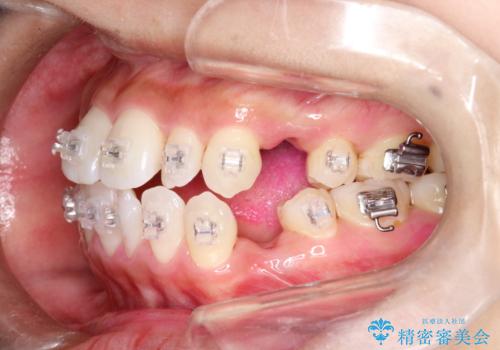

ワイヤー矯正治療中に気になる口臭をPMTCで予防

担当医 歯科衛生士